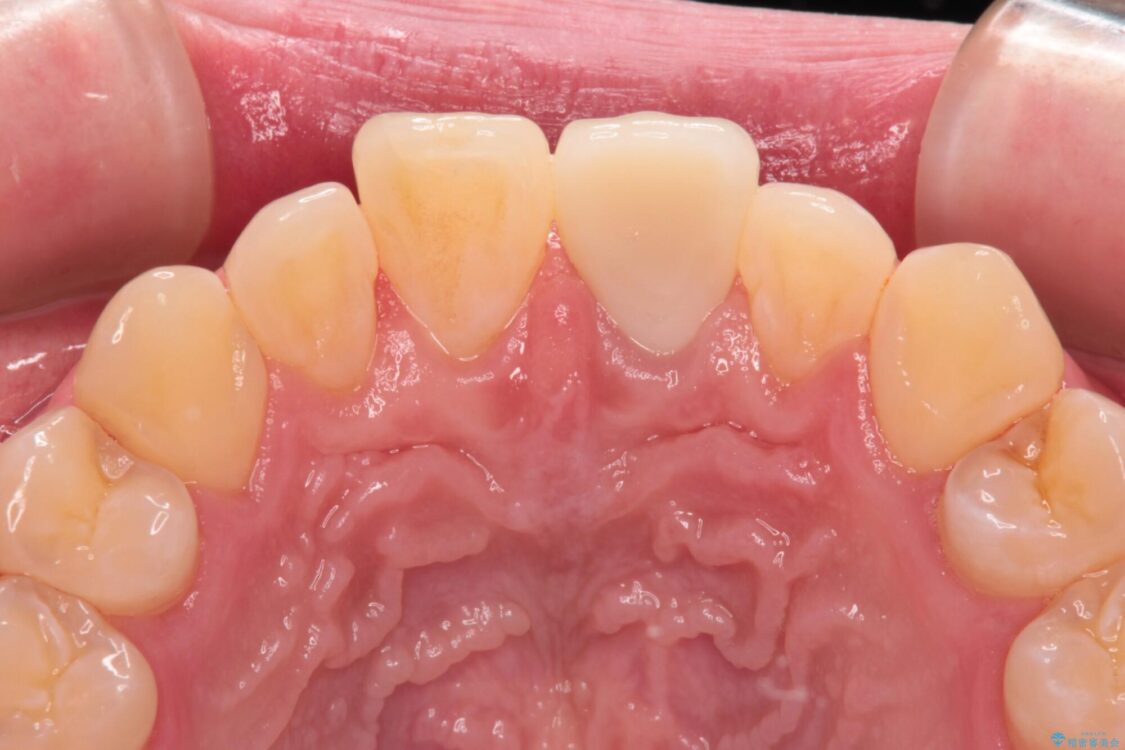

神経を取り除いたことで変色した前歯を気にして来院された患者様です。

神経を取り除いた歯は時間とともに変色してきます。

クリーニングやホワイトニングでは改善できないため、オールセラミッククラウンなどによる補綴治療が必要となります。

治療後

• 変色した前歯をオールセラミッククラウンに 治療後画像